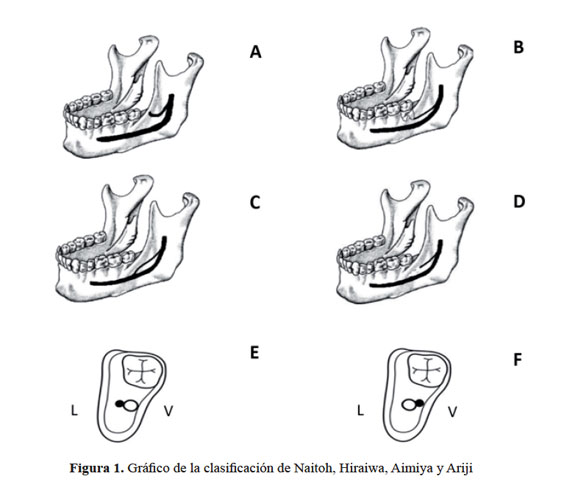

Los investigadores Naitoh et al., en el año 2009 contribuyen con la clasificación más reciente del conducto mandibular bífido además de ser la primera clasificación realizada mediante TCHC donde consideraron 4 tipos (Figura 1) (15).

Tipo 1 (Canal retromolar): Consiste en una bifurcación del canal mandibular en la región de la rama mandibular, no alcanza piezas dentales, el conducto realiza una curva y alcanza la región retromolar (Figura 1 (A)).

Tipo 2 (Canal dental): En este tipo la bifurcación del canal mandibular alcanza el ápice de la raíz del segundo o tercer molar (Figura 1(B)).

Tipo 3 (Con y sin confluencia anterior): Bifurcación del conducto mandibular, el cual continúa su recorrido hacia el sector anterior, luego puede volver a unirse o no con el conducto mandibular principal (Figura 1 (C y D)).

Tipo 4 (Canal bucal - lingual): Bifurcación del conducto mandibular, el cual recorre por el sector lingual o bucal del cuerpo de la mandíbula y del canal mandibular principal (Figura 1 (E y F))